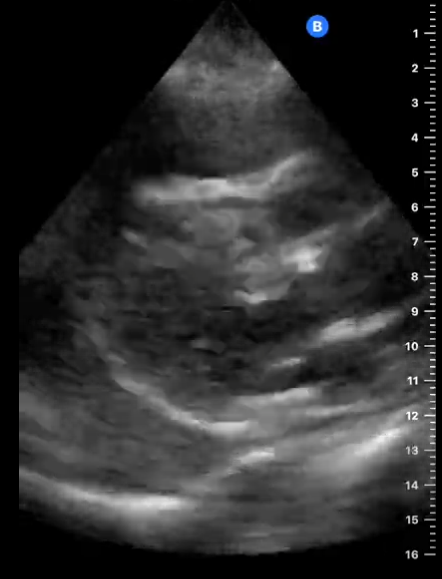

En la ecocardiografía se aprecia latido cardiaco con intercambio de flujos muy disminuido y el miocardio movilizándose en el interior del derrame pericárdico contenido sin taponamiento.

En este caso tenemos un cuadro de derrame pericárdico con repercusión hemodinámica pero apreciándose latido cardíaco y suficiente contractilidad como para no incurrir en taponamiento cardíaco que hubiera supuesto una emergencia vital para la paciente.